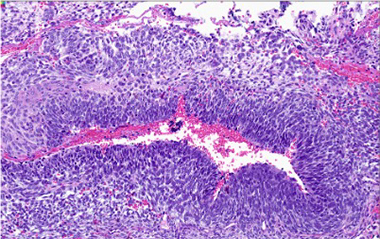

B. Complex cystic architecture (low power)

Pheochromocytoma was identified comprising 50% of tumor volume. In addition, the lesion contained a primitive round cell component possibly neuroblastoma with focal neuroblastic differentiation (20%) and a malignant peripheral nerve sheath tumor (30%) with heterologous elements (cartilage). Areas of hemorrhage and necrosis were noted resulting in cystic degeneration.